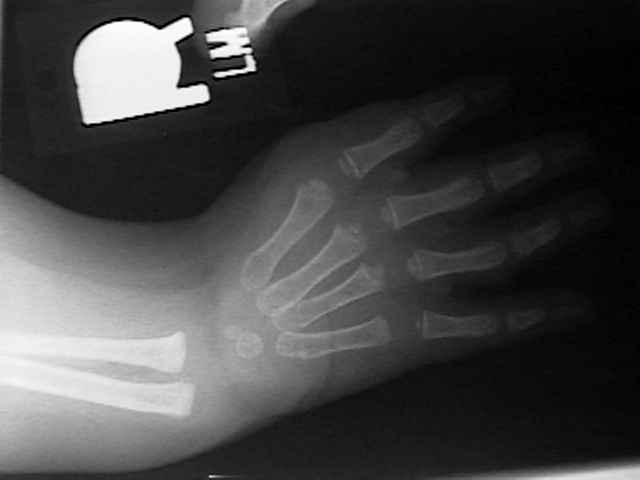

Radiographs

HL6